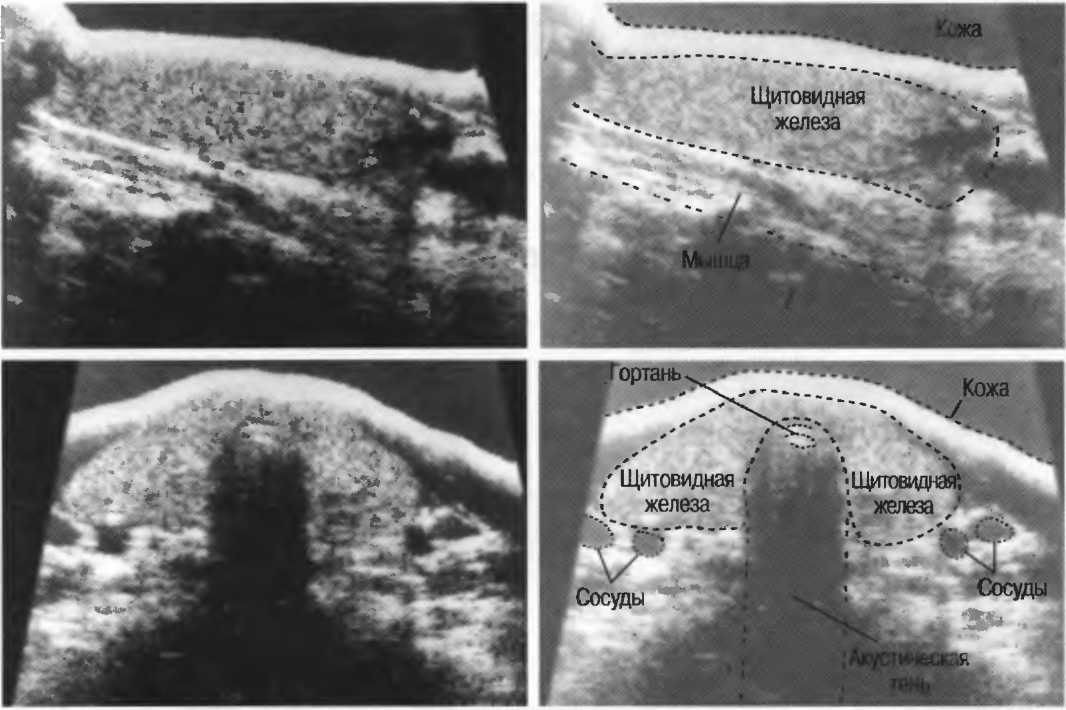

1. Линейный датчик. Срезы при использовании таких датчиков имеют форму прямоугольников. Эти датчики наиболее удобны в акушерских исследованиях, а также при исследовании щитовидной и молочных желез (рис. 7а).

Рис.7а. Срезы прямоугольной формы, получаемые при использовании линейного датчика.

Акустическое усиление и акустическая тень

Плотные материалы, такие как кости или камни, дают акустическую тень на структуры, расположенные сзади, в результате того что ультразвуковая волна не проходит через них. Этот феномен получил название «акустической тени». Например, ребра могут экранировать ультразвуковой поток, поэтому структуры, расположенные за ними, нужно исследовать в косом направлении по межреберным промежуткам (рис. 10б,в).

Тени

Кости, камни и кальцинаты дают акустическую тень. Ультразвук не может проходить через кость, если она только не очень тонкая (как, например, кости черепа у новорожденного). При необходимости рассмотреть структуры, расположенные глубже, необходимо использовать различные углы наклона датчика (рис. 17а,б).